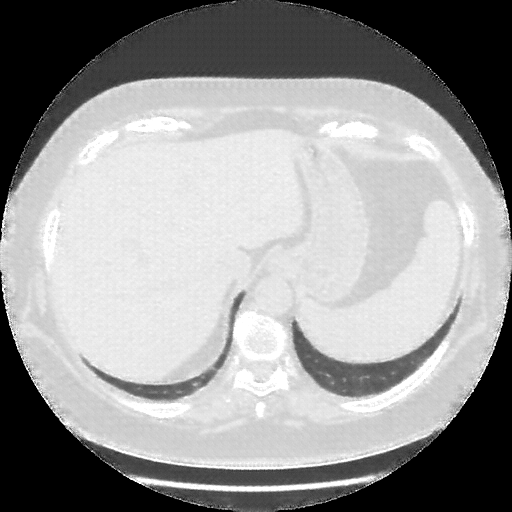

Image Grid

4Γ—3 grid: Rows show different image types (Original NATIVE, Reconstructed NATIVE, Original VENOUS, Generated VENOUS), Columns show windowing techniques (No Window, Lung Window, Mediastinum Window)

Original NATIVE CT scan (input)

No window - Raw intensity values